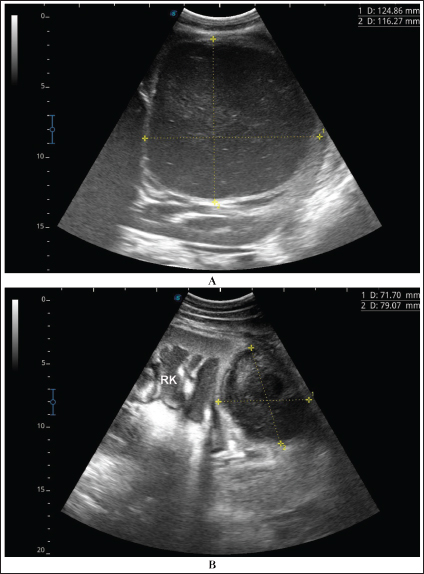

Fig. 4. Ultrasonographic findings of camel number 1 with abscessation of the right kidney. A large abscess was found in image A measuring 12.5 × 11.6 cm with hypoechoic contents and a thick capsule. The abscess in image B compresses the parenchyma of the right kidney (RK) and measuring 7.2 × 7.9 cm with echogenic contents and a thick capsule.

A detailed description of the renal abscesses is presented in Figures 410. Figure 4 shows sonographic findings in camel number 1 with abscessation of the right and left kidneys. A large abscess measuring 12.5 × 11.6 cm with hypoechoic contents and a thick capsule was detected. A second abscess in the same camel was imaged compressing the parenchyma of the right kidney and measuring 7.2 × 7.9 cm with echogenic contents and a thick capsule. Figure 5 shows ultrasonographic results in camel numbers 2 and 4 with right kidney abscesses. The lesions in camel number 2 appeared markedly large, compressing the renal parenchyma, with echogenic contents and a thickened capsule. The lesion in camel number 4 appeared to compress the renal parenchyma of the right kidney, measuring 6.7 × 8.2 cm with echogenic contents and a thick capsule. In addition, Figure 6. clarifies sonographic findings in camel number 6, where the abscess appeared within the right kidney. The contents were heterogeneous, but the capsule could not be imaged. The urinary bladder in the same animal was imaged with echogenic deposits that appeared highly echogenic compared with the echogenic urine.